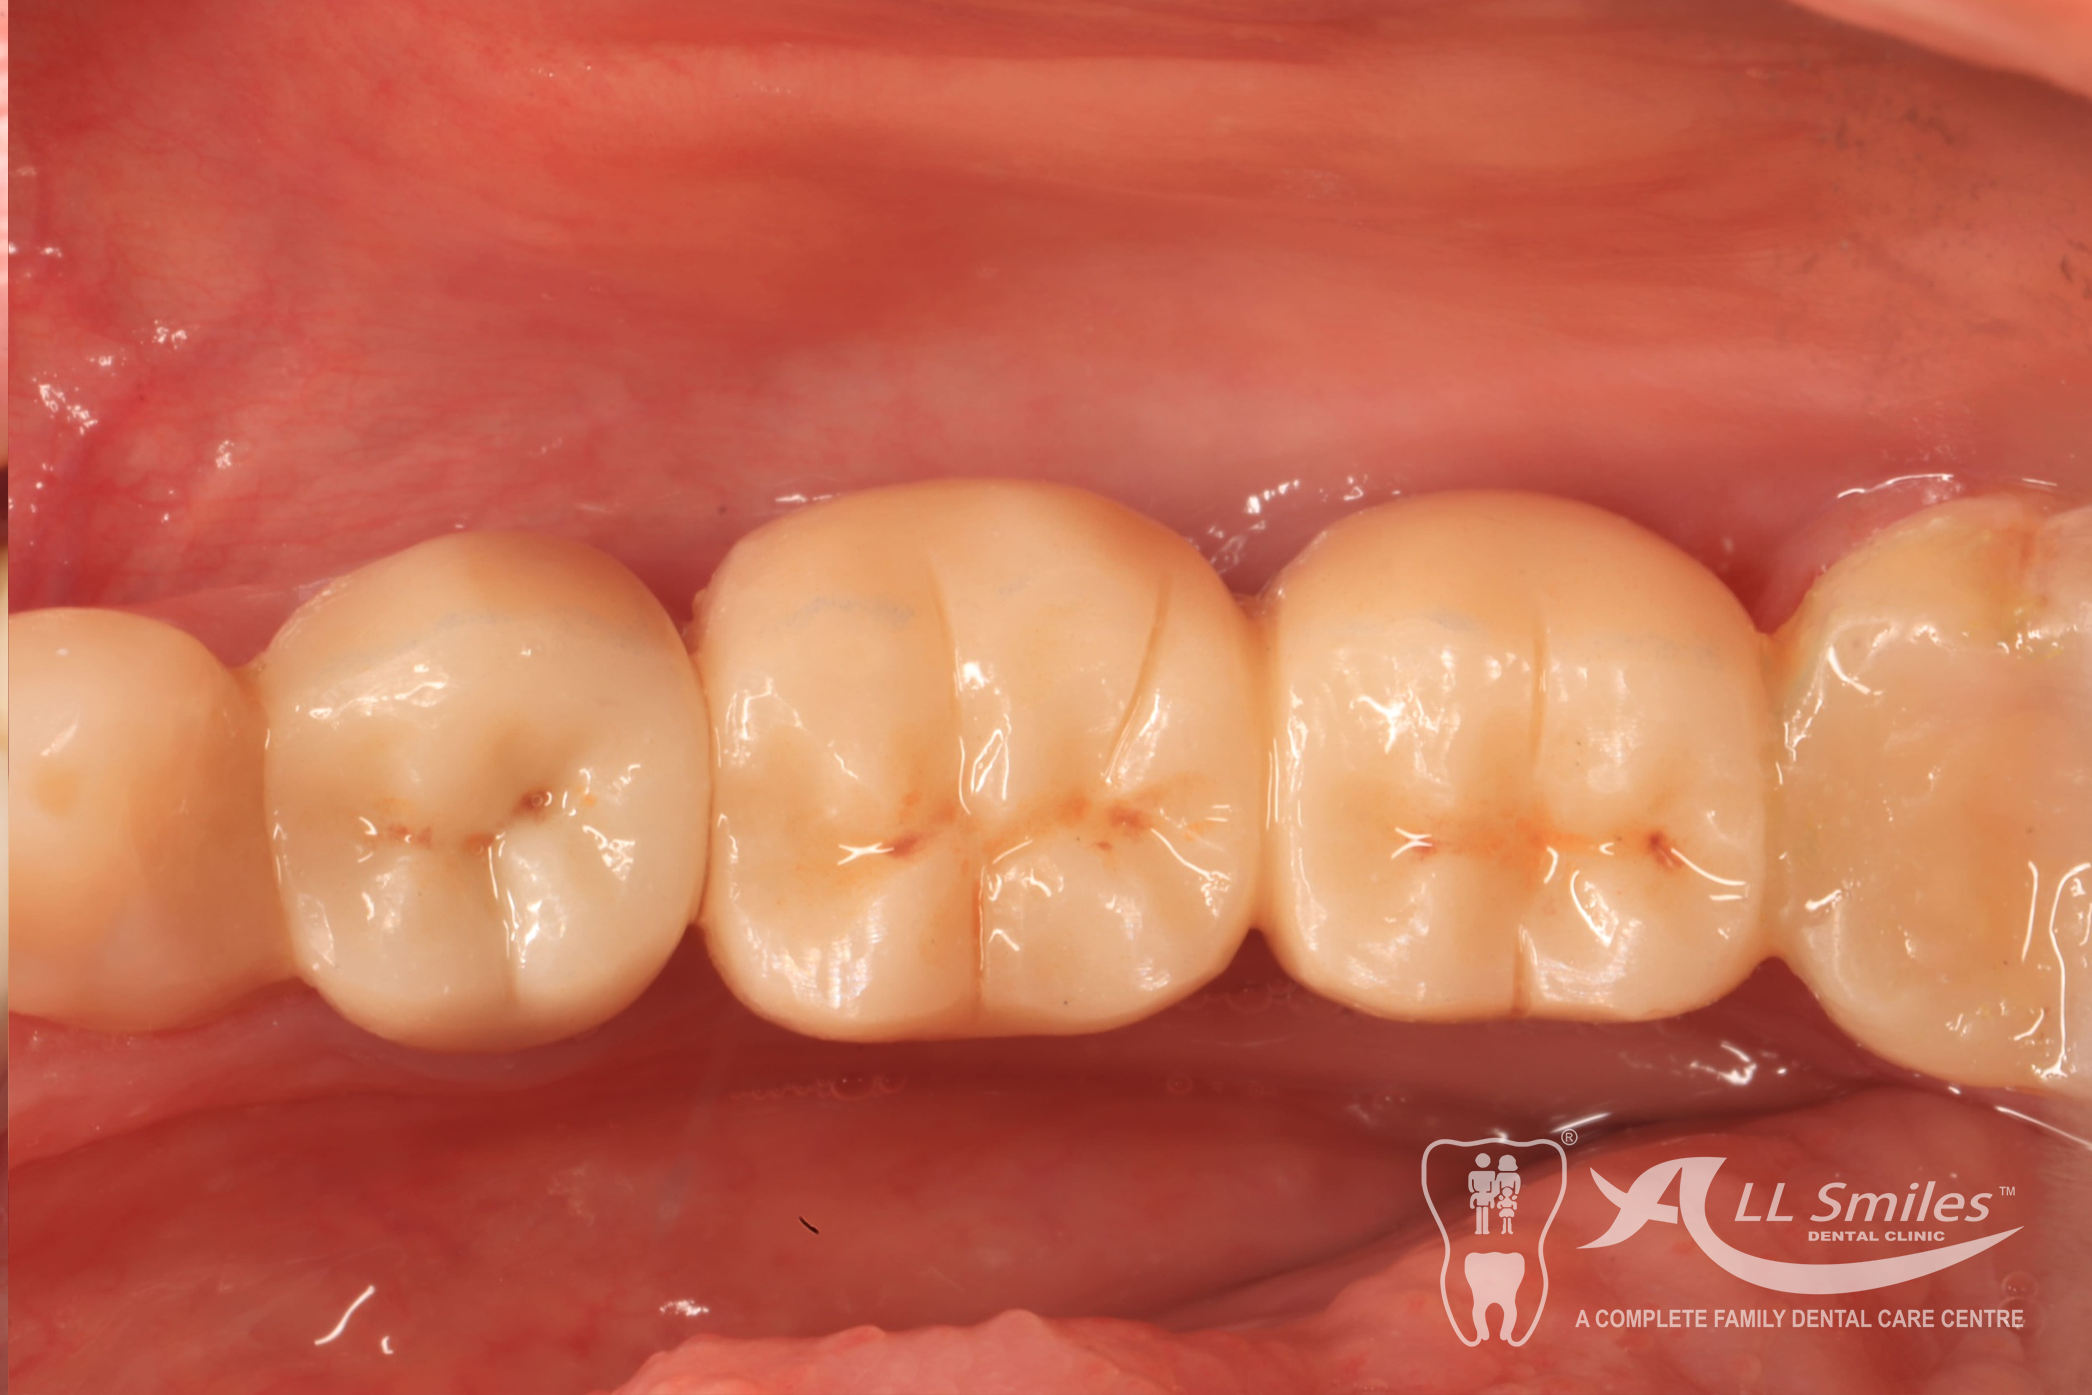

This usually does not take any longer than any routine treatment. A temporary restoration closes the gap until the implant is healed. Then the final tooth crown is fixed in place – permanently . With the new root it is fixed firmly in the jaw and feels identical to your natural teeth.